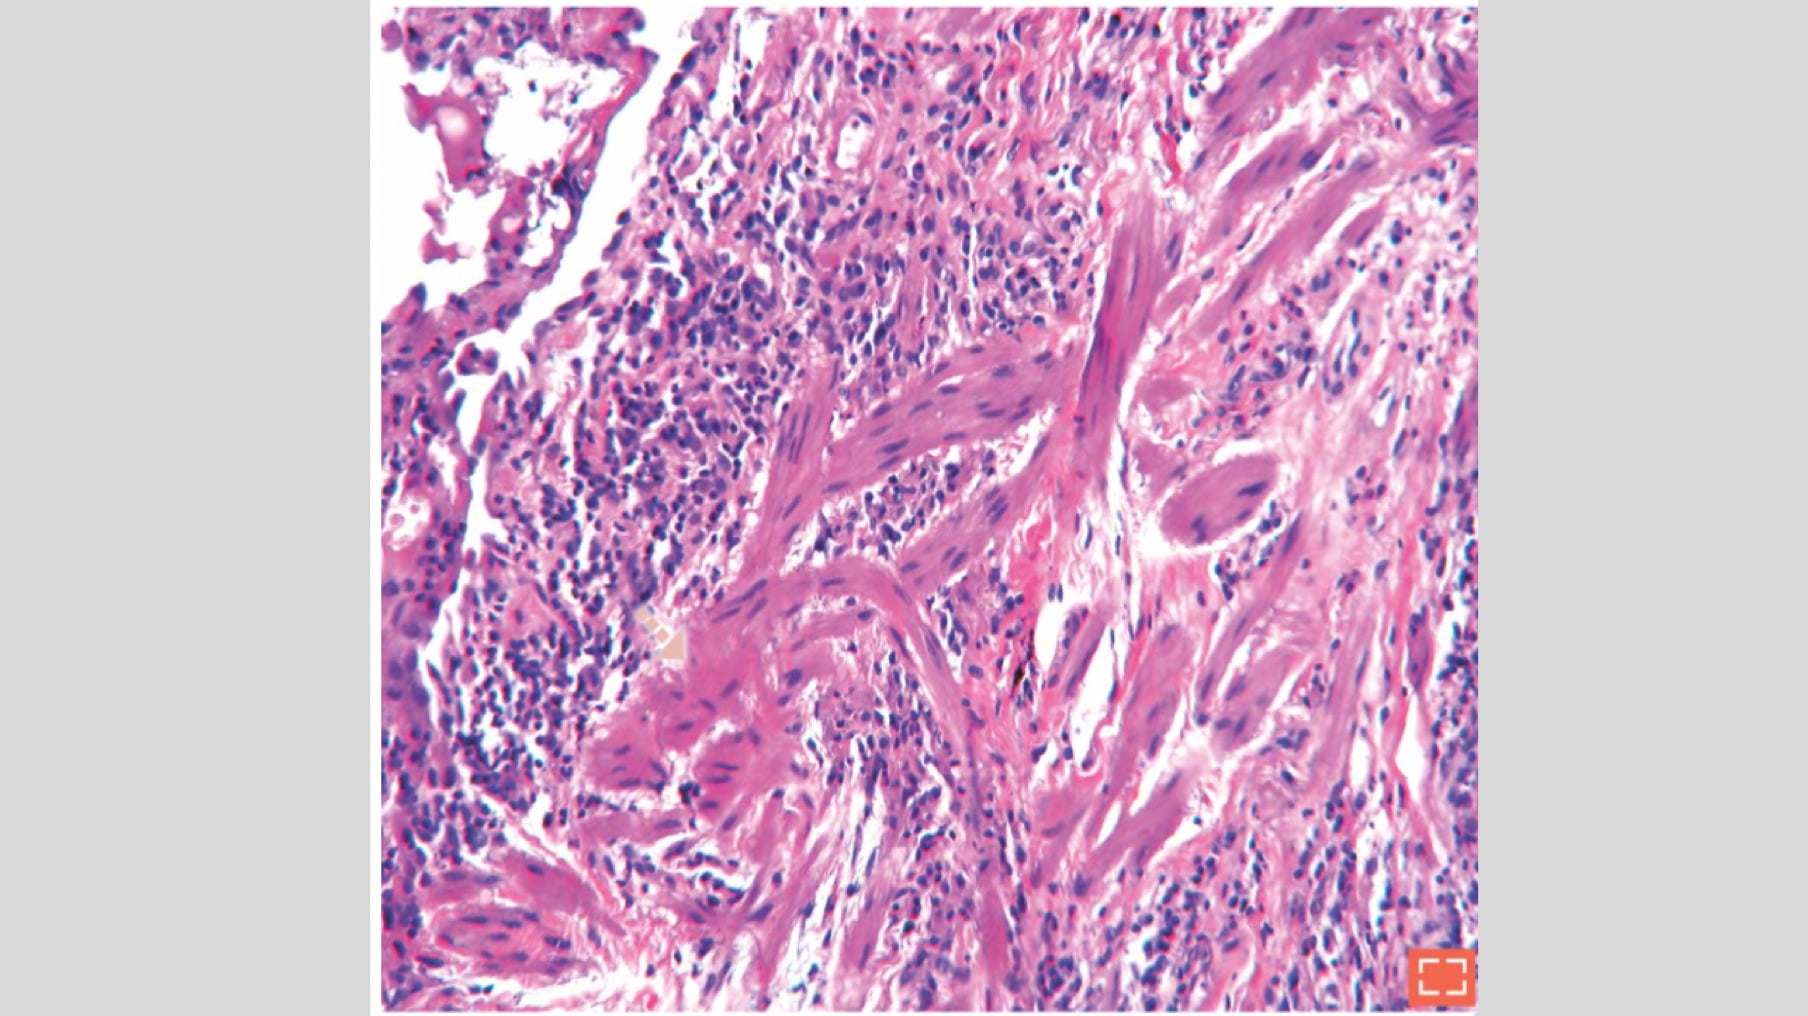

Elementary Lesions Smooth muscle hyperplasia (I) Characteristics Bundles of hyperplastic smooth muscles Synonyms: “myomatosis”, “muscular cirrhosis” Destruction of the normal alveolar structure by fibrosis “Myomatosis” Zoom BI GDS Side Navigation In This Section Patchwork pattern Architectural distortion Honeycomb change Bronchial epithelial metaplasia Fibrosis Smooth muscle hyperplasia (I) Smooth muscle hyperplasia (II) Vascular changes Fibroblast focus Home Vores lægemidler Education Imaging Atlas Smooth muscle hyperplasia (I)